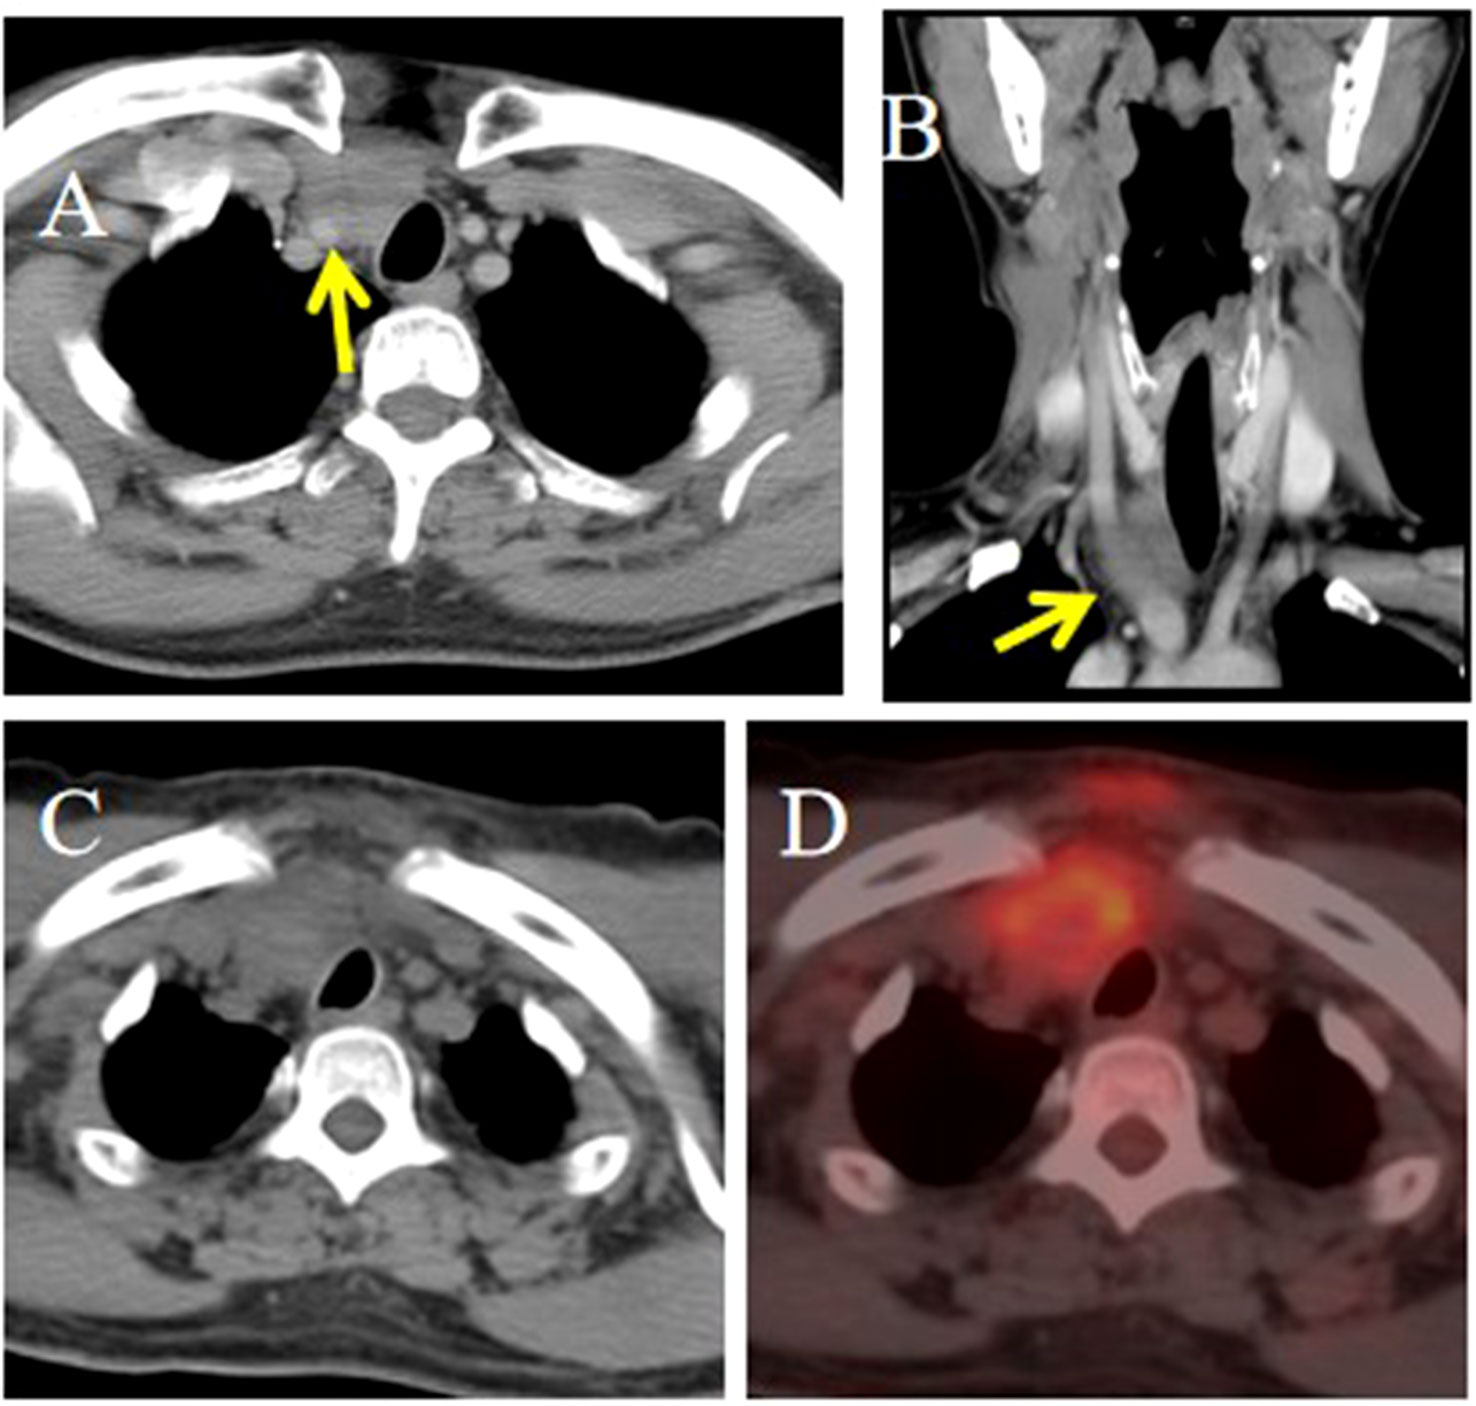

Objective: To summarize the clinical characteristics and imaging features of intrathyroid thymic carcinoma (ITTC), along with diagnostic and therapeutic approaches, to increase awareness of this rare disease. Methods: We retrospectively analyzed 14 patients with ITTC confirmed by core needle biopsy (CNB) and surgery combined with immunohistochemistry. The clinical and imaging findings, treatment, pathological findings and follow-up data of these patients were reviewed. Results: Thirteen patients were newly diagnosed and one relapsed at the original surgical site. All tumors were solitary, mostly located in the lower neck or upper chest, often in the tracheoesophageal groove with or without extension to the thyroid’s lower pole, and approximately two-thirds of patients presented with hoarseness. On CT, most lesions appeared as irregular, low-density soft-tissue masses, with calcification in two cases; contrast-enhanced CT revealed mild heterogeneous or homogeneous enhancement, and over half exhibited an arc-shaped interface with adjacent thyroid tissue. Most tumors were locally advanced, invading muscles, the supraclavicular fossa, tracheoesophageal groove, esophagus, tracheal wall, or mediastinal vessels. The diagnostic accuracy of fine-needle aspiration biopsy (FNAB) was low, whereas core needle biopsy (CNB) combined with immunohistochemistry was reliable. Ten patients underwent radical surgery, of whom three received adjuvant chemoradiotherapy and four adjuvant radiotherapy; four patients received radical chemoradiotherapy, and one received combined therapy including anlotinib, a novel tyrosine kinase inhibitor. The median follow-up was 86 months (range, 25–146), and three surgically treated patients developed local recurrence or pulmonary metastasis. Conclusion: CNB combined with immunohistochemistry is recommended when the characteristic and imaging manifestations suggest a diagnosis of ITTC. Especially for locally advanced cases, imaging-based diagnosis can be useful for analysis and to guide treatment.